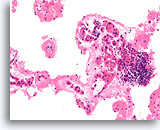

Afbeelding 14

Benigne, hyperplastisch/adenomatoïde nodule, schildklier FNA, celblok.

Let op het afgeplatte cytoplasma in e microfollikels vergeleken met het kubusvormige tot cilindrische cytoplasma van het macrofolliculaire epitheel linksboven. Let ook op het waterige colloïde in één follikel (pijl) vergeleken met het dicht opeengepakte colloïde in de microfollikels.

40X

Afbeelding 14

Benigne, hyperplastisch/adenomatoïde nodule, schildklier FNA, celblok.

Let op het afgeplatte cytoplasma in e microfollikels vergeleken met het kubusvormige tot cilindrische cytoplasma van het macrofolliculaire epitheel linksboven. Let ook op het waterige colloïde in één follikel (pijl) vergeleken met het dicht opeengepakte colloïde in de microfollikels.

40X